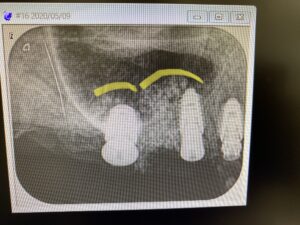

綺麗なドーム状にシュナイダー膜を持ち上げ造骨組織が収まっています。